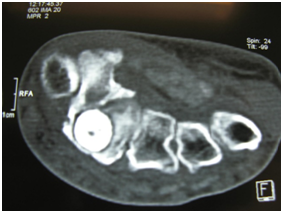

X ray (Figure 2) and CT scan (Figure 3) (Figure 4) done revealed a smooth dense cortical rounded bony lesion at the base of the second metacarpal bone with a clear even rounded edge characteristic of Bone Island. Surgical Exploration via dorsal approach, revealed erosions of the posterior cortex of the lower metaphysis of the second MC bone by the lesion (Figure 5) which was easily removed en mass (Figure 6) (Figure 7) and the cavity left (Figure 8) was filled with ipsilateral punched iliac bone graft (Figure 9).

Figure 2

Figure 3